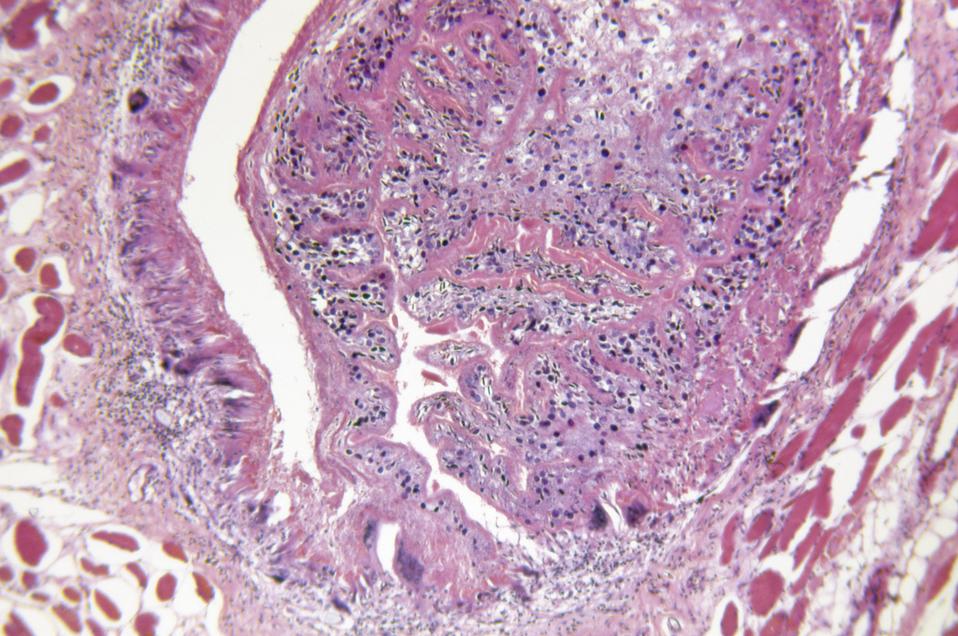

No, it is not normal to have all those white spots in your head. Each white spot is a cyst, created by the larvae of Taenia solium, otherwise known as the pork tapeworm. Using ultrasound, the doctors also found cysts in the patient’s eye and testis. If you must “in cyst” on knowing the medical term for this condition, it’s cysticercosis. Cysticerci are these cystic lesions formed by the young-uns of the pork tapeworm. Neurocysticercosis is when these lesions occur in the brain. These cystic lesions can cause inflammation and damage to the surrounding areas. If its in the brain, these can damage the brain, leading to a variety of neurological symptoms. If its in the testes, ouch.